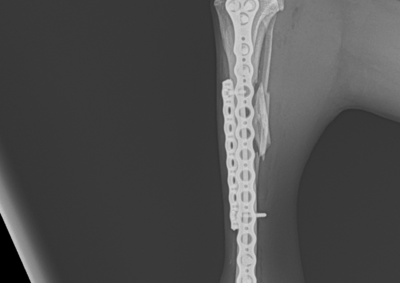

注意 ボタンをクリックした先に、治療中および手術中の画像が説明で使用されている場合がございます。 そのような画像に弱い方は閲覧なさらないようお願いいたします。 整形外科 若齢犬の橈骨固定術 #271 整形外科 前十字靭帯断裂(中型犬)に対するCBLO #255 整形外科 超小型犬に対する上腕骨遠位Y字骨折 整形外科 大型犬の前十字靭帯疾患(慢性経過)に対するCBLO #254 整形外科 橈骨固定術 #270 整形外科 膝蓋骨内方脱臼に対する人工滑車置換術 PGR #23 整形外科 犬の前十字靭帯(疾患)部分断裂に対するCBLO #253 整形外科 犬の前十字靭帯断裂に対するCBLO #252 整形外科 膝蓋骨内方脱臼+前十字靭帯断裂に対するPGR#22・LSS 整形外科 大腿骨骨折 整形外科 橈骨固定術 #269 整形外科 上腕骨外顆骨折の癒合不全 123456> 症例カテゴリー 放射線治療整形外科軟部組織外科脳神経外科内科腫瘍外科救急・集中治療リハビリテーション科腫瘍内科内視鏡科脳神経科呼吸器外科中医・漢方猫の腎移植循環器科